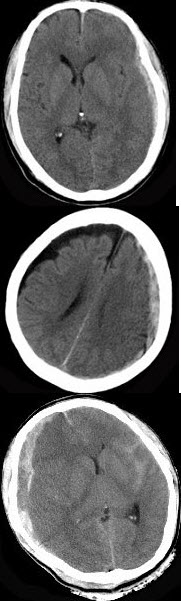

九个月男孩,头明显增大,前囟大而且鼓出,头下垂,双眼有落日征,头部叩诊有破壶音。四肢活动少,双侧Babinski征阴性,体温正常。

(单选题)根据CT表现可能的诊断( )

A:先天性脑积水

(单选题)有效的症状治疗是( )

A:脑室心房分流术